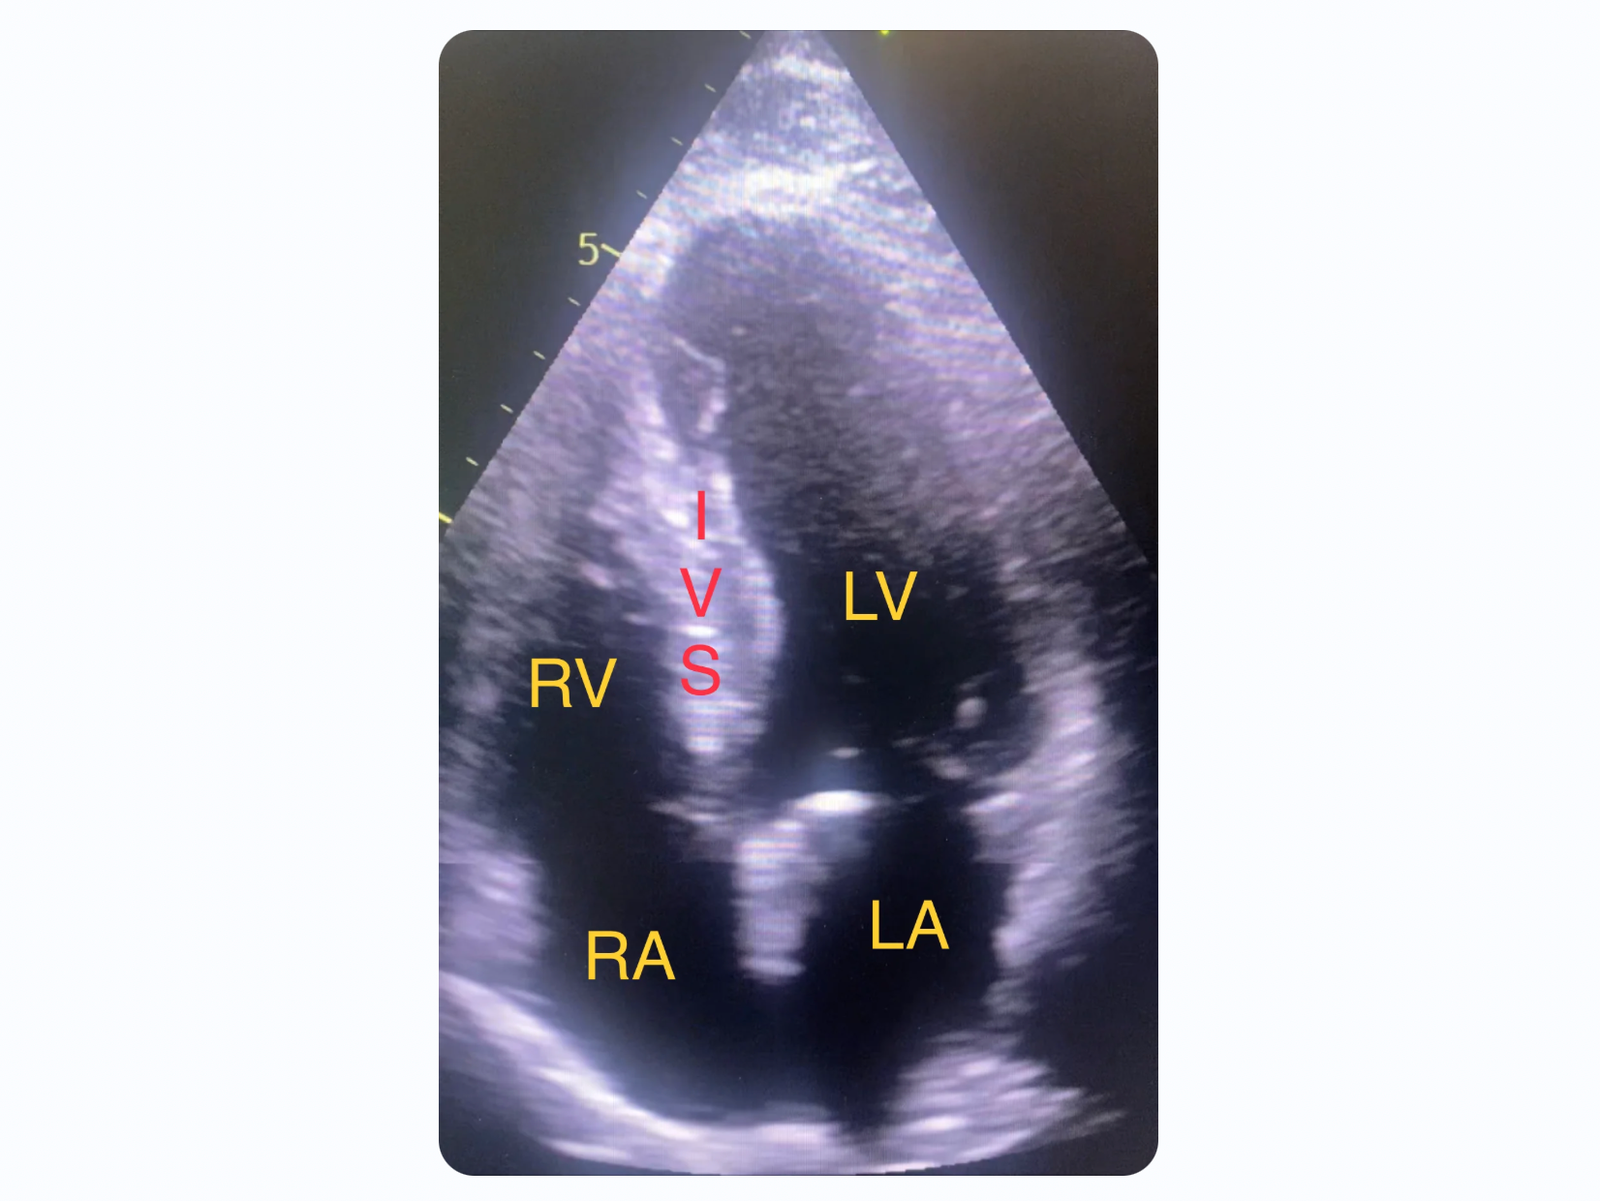

Below I have reproduced a still frame image from the bedside Echo done on today’s patient. The top of the image is closest to the echo probe. The apex of the heart is at the top of the image with the base at the bottom. The heart chambers are annotated. (RA = right atrium. RV = right ventricle. LA = left atrium. LV =left ventricle. IVS = interventricular septum.)

This video shows the regional wall motion abnormality of the distal septum and apical region of the left ventricle. The distal septum appears thickened. This is not due to hypertrophy. The myocardium appears thickened (pseudohypertrophied) due to myocardial edema. The edema also makes the necrotic myocardium less echo dense making it appear less “white”.